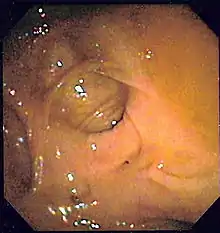

Colonoscopy

Colonoscopy is the test of choice in the majority of patients with acute Lower GI bleeding as it can be both diagnostic and therapeutic. The diagnostic accuracy of colonoscopy in lower GI bleeding ranges from 48% to 90%, and urgent colonoscopy appears to increase diagnostic yield. This wide range in yield is partially explained by different criteria for diagnosis, as often if no active bleeding, nonbleeding visible vessel, or adherent clot is found, bleeding is attributed to a lesion if blood is present in the area. The presence of fresh blood in the terminal ileum is presumed to indicate a non colonic source of bleeding. The overall complication rate of colonoscopy in acute lower GI bleeding is 1.3%. Bowel preparation is safe and well tolerated in most patients. The complication rate of colonoscopy in an unprepped colon may be higher. About 2–6% of colonoscopy preparations in acute lower GI bleeding are poor. Between 4 and 8 L of Golytely should be administered orally or via nasogastric tube until the effluence is clear.[9]